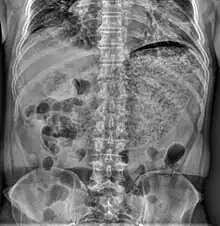

Simple abdominal X-ray shows gastric distension with a large amount of material in the stomach, suggesting severe gastric hypomotility